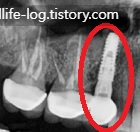

임플란트 식립 x-ray사진

사진에서 보시는 것과 같이 자연치아 뿌리가 아닌 인공뿌리를 잇몸뼈에 식립 후 저작이 가능하게 보철물까지 완성해 놓았습니다. 이렇게 임플란트는 자연치아를 발치하게 되었을 때 필요한 사항인데 왜 자연치아를 발치해야 하는지에 대하여 알아볼게요!